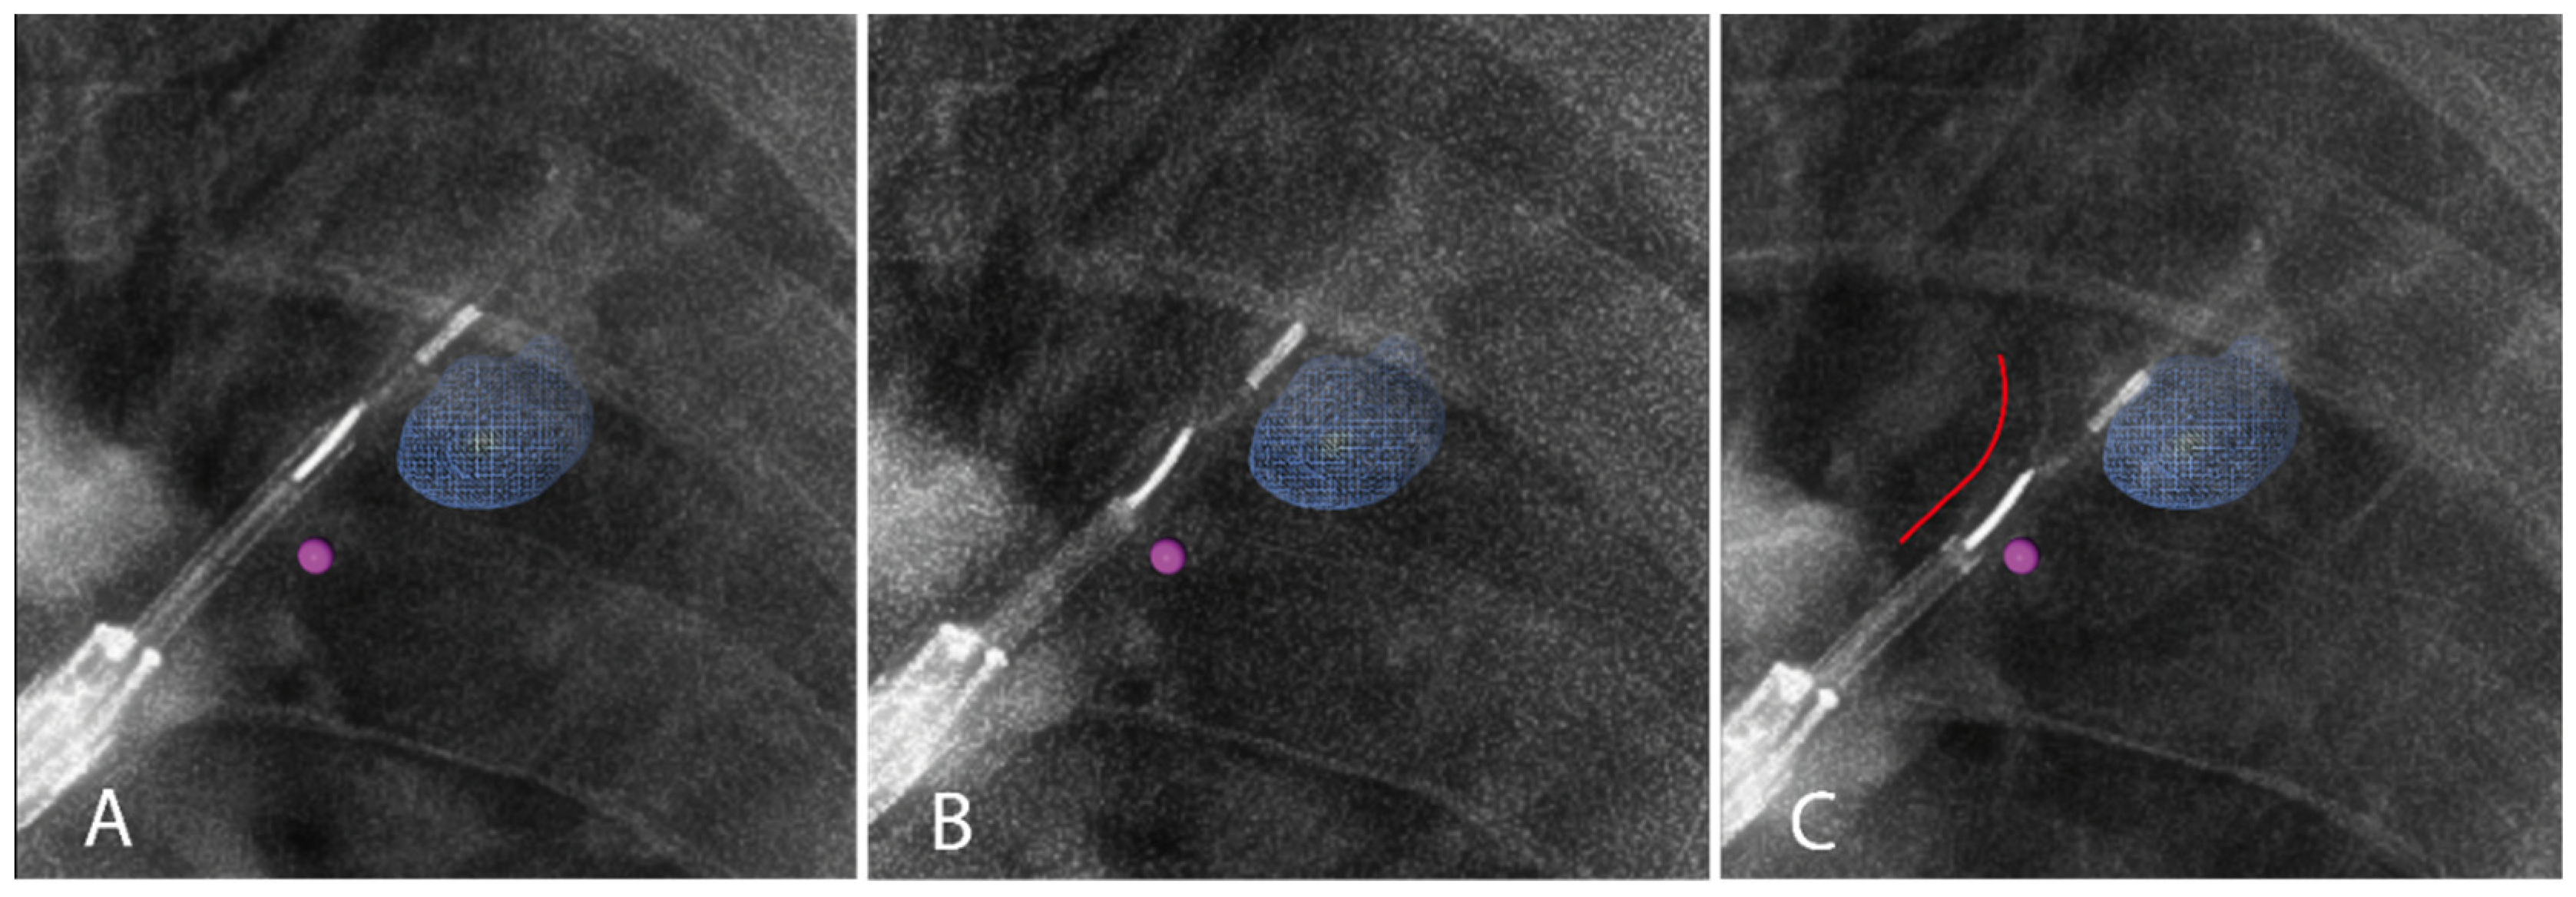

2.3.2. Imaging Tracer Injection

3.2.2. Iodinated Contrast Injection

| Injection visible on fluoroscopy, n (%) | 15 (100%) | ||

| Leakage visible on fluoroscopy, n (%) | 4 (26.7%) | ||